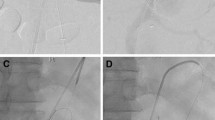

This is a case of an in situ laser fenestration for two target vessels (superior mesenteric and right renal arteries); in this case, landmarks were placed at the ostia places of the celiac trunk, the superior mesenteric artery and the right renal artery. (The left kidney was atrophic and non functional.) First, the Aptus catheter was placed in front of the superior mesenteric artery based on image fusion coronal and sagittal views and the guide wire was placed into the target vessel after perforation, here the superior mesenteric artery (A). A cutting balloon was placed to enlarge the hole (B) followed by a balloon dilatation. A long sheath was placed into the target vessel (C) before the stent placement (D) and deployment (E). The Aptus catheter was then placed in front of the right renal artery on frontal and sagittal views before perforation (F)